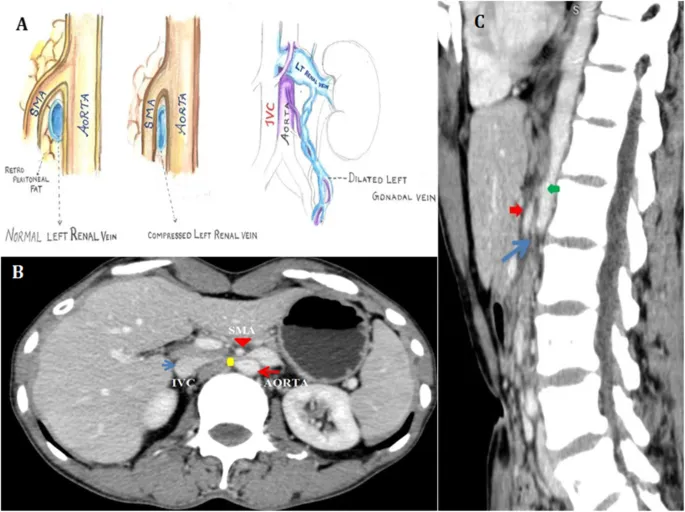

Axial Slice @ L2/L3 - The Nutcracker Crunch

- Key Structures: Kidneys, renal vessels, aorta, IVC, superior mesenteric artery (SMA), and duodenum.

- Vascular Relationship: The left renal vein (LRV) courses between the SMA anteriorly and the abdominal aorta posteriorly.

- Clinical Correlation: Compression of the LRV in this "nutcracker" can lead to renal venous hypertension, causing hematuria and flank pain.

⭐ Exam Favourite: Nutcracker syndrome is a key cause of unexplained left-sided varicocele, as the left gonadal vein drains into the high-pressure LRV.

- The left renal vein's path between the aorta (posteriorly) and SMA (anteriorly) is a classic anatomical relationship (Nutcracker syndrome).